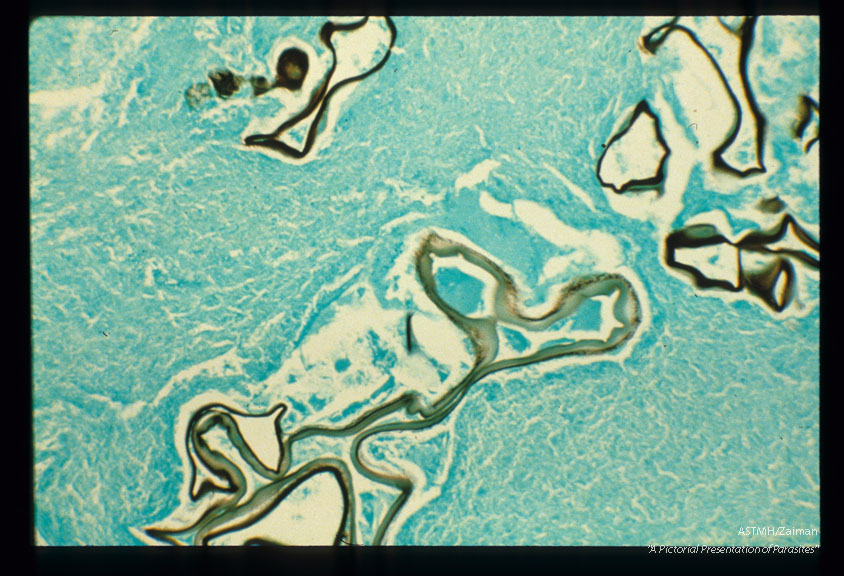

Silver methenamine stain of infected human liver.

Echinococcus multilocularis

Description: Silver methenamine stain of infected human liver.